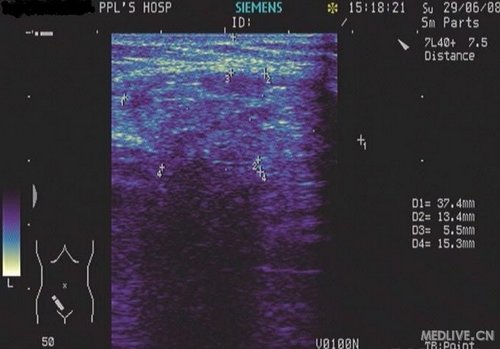

患者,男,75岁,自觉右下腹包块,不适,来我院就诊,自述1年前做过阑尾手术。

超声检查:

右下腹壁包块扫查:

右下腹壁软组织内可见一大小37.4mm×37.3mm×15.3mm欠均匀稍强回声(距体表约5.5mm),通过一宽约15.3mm回声中断与右下腹腔相通。

CDFI:上述稍强回声内可见少许星性状血流信号。

超声提示:右下腹壁异常回声,考虑腹壁切口疝,请结合临床